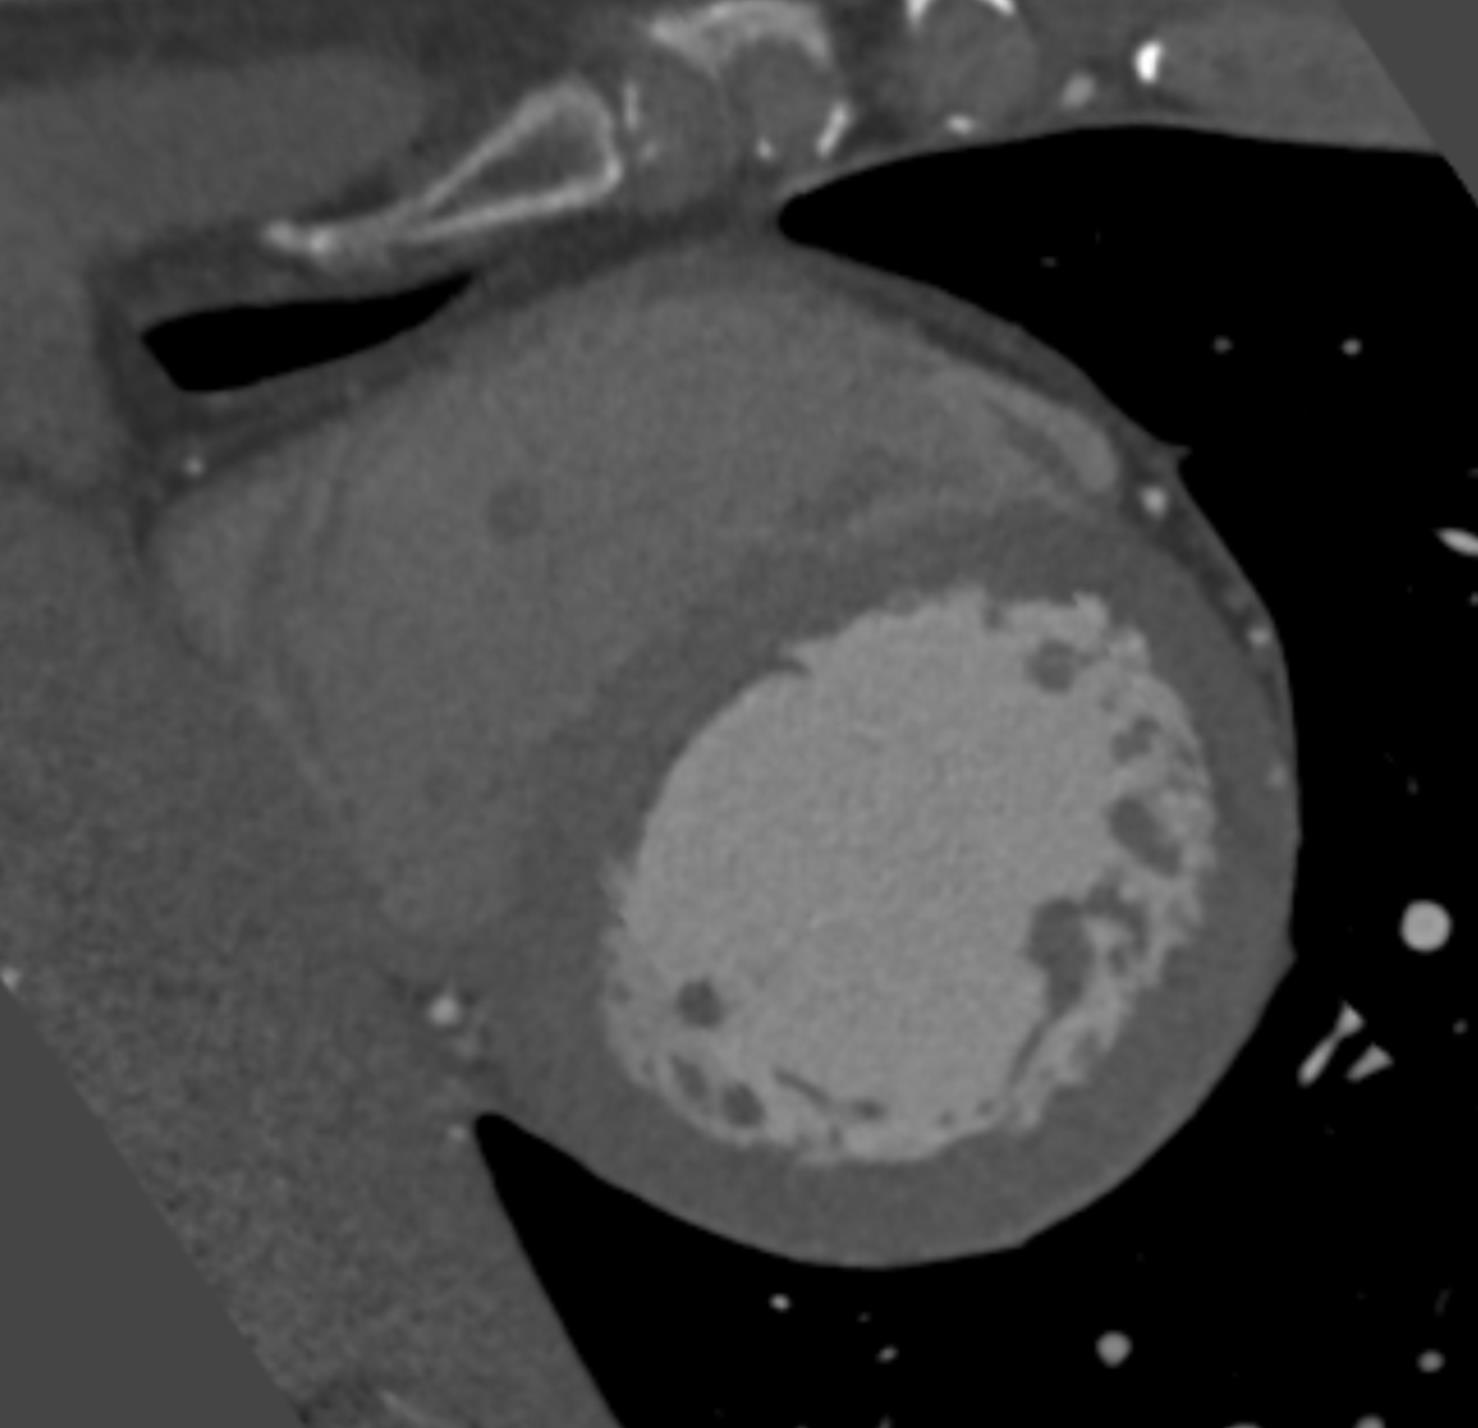

To train, validate and test the segmentation of LV myocardium, the myocardium was manually annotated in 40 randomly selected CCTA scans. Manual annotations were performed by a trained observer using custom-built software created with the MeVisLab111http://www.mevislab.de platform. Following clinical workflow, annotations were performed in the short axis view of the heart, while excluding myocardial fat, papillary muscles and the trabeculae carneae. Segmentation was performed by manually placing points along the endocardium and epicardium in every third image slice. From the defined points, closed contours for the endocardium and the epicardium were created by cubic spline interpolation. The contours were propagated to the adjacent slices where they were manually adjusted when needed by moving existing or placing new points. Reference LV myocardium contained all voxels enclosed by the manually annotated endocardial and epicardial contours. Fig. 3 illustrates a typical short axis view of the LV myocardium and the annotated manual reference.

Manual annotation of the LV myocardium is a time-consuming task. Therefore, automatic segmentation was evaluated quantitatively in a subset of test scans with manually defined reference and qualitatively in all test scans.

Quantitative evaluation was performed using the Dice coefficient, as an overlap measure between reference and automatically segmented volumes. In addition, the mean absolute surface distance (MAD) between the reference and automatically segmented LV boundaries was computed.

Qualitative evaluation was performed by an expert who visually inspected and graded the automatic segmentation using the quality grades as defined by Abadi et al. [2010].

Fig. 8 illustrates segmentation results. Quantitative evaluation of the segmentation performed on the 20 test scans resulted in a Dice coefficient of and a MAD of mm. Qualitative evaluation of the segmentation was performed in all 146 test scans. Results are summarized in Table 2.